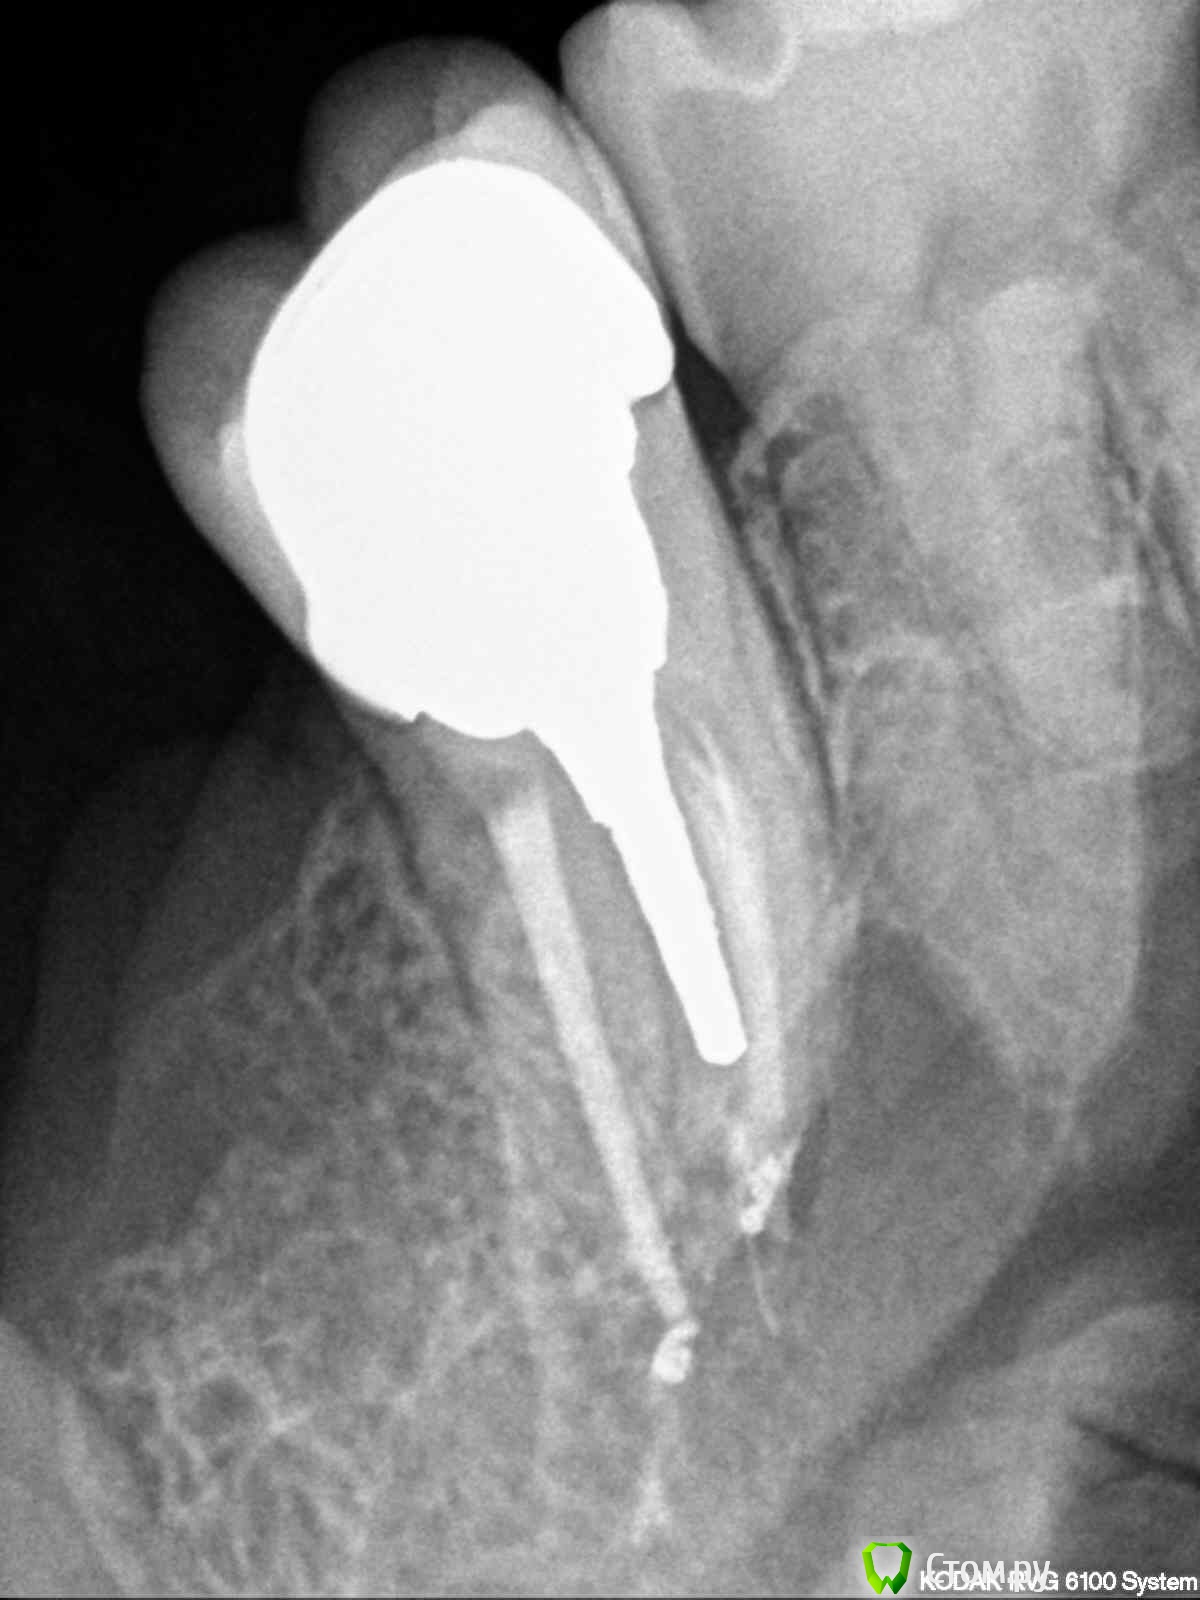

englishlady Опубликовано 12 марта, 2014 Поделиться Опубликовано 12 марта, 2014 Уважаемые врачи, здравствуйте.Существет 27 зуб, на который летом была установлена коронка. Начиная с ноября-декабря, область десны вокруг зуба стала ныть, при чистке зубов десна в этом месте тоже более болезненна, периодически этот зуб отдает в скулу и пазуху. Но эти ощущения не очень сильные, периодически проходят, обезболивающие я пока не принимаю.На ряде форумов мне сказали, что у этого зуба периодонтит, что перелечивать его бесполезно. Может помочь только резекция или имплантация. Но когда я прихожу на прием в разные клиники, то врачи не видят проблем, поскольку зуб не реагирует ни на холод, ни на перкуссию. Я выкладываю прицельные снимки Есть несколько вопросов:1) насколько будет результативна резекция, если она нужна?2) если лечить его бесполезно, то при имплантации какой понадобится синуслифтинг?3) какой из хирургических вариантов предпочтительнее? На одном форуме врач сказал, что резекция в моем случае плохой вариант, поскольку у меня слишком близко расположена пазуха.4) возможно ли его просто перелечить (например с использованием микроскопа).Заранее спасибо за ваши ответы Ссылка на комментарий

Mane Опубликовано 14 марта, 2014 Поделиться Опубликовано 14 марта, 2014 описанные вами симптомы скорее всего говорят об обострении хронического периодонтита в области 27. резекцию корня делать не нужно - уж слишком безрезультативна эта операция. Но в вашем случае кроме того она может быть еще и нереализуема технически - чтоб судить о том можно ли ее реализовать нужна КТ. но я в этом не вижу смысла. так как все равно бы делать резекцию не стал. так как рано или поздно зуб придется удалить (уже после резекции). попытаться перелечить у грамотного эндодонтиста - вот это рабочий вариант. но судить о рацинальности такого перелечивания опять нужно по КТ. если зуб на удаление - то ДА, вам понадобится синус - лифтинг в случае имплантации. при желании все можно сделать за одну процедуру - удаление и синус - лифтинг с имплантацией. но опять же. судить о том чтоб все за раз можно только по КТ. вывод - делайте КТ и снимки в студию! Ссылка на комментарий

Mane Опубликовано 20 марта, 2014 Поделиться Опубликовано 20 марта, 2014 Скорее всего стоит. Но окончательно ясно станет после снятия коронки. Ссылка на комментарий